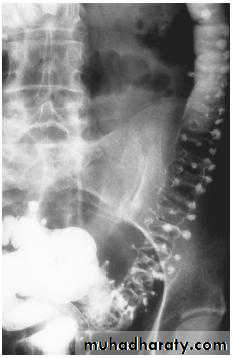

11. Pancreatic calcification: occur in chronic pancreatitis & diagnosed from it's position

Chronic pancreatitis

It result in fibrosis, calcifications, and ductal stenosis and dilatation.Pseudocysts are seen.

The calcification often recognizable on plain x ray film, but more obvious on CT.

The gland may enlarge focally or generally. The gland may atrophied. The pancreatic duct may be enlarged and irregular.